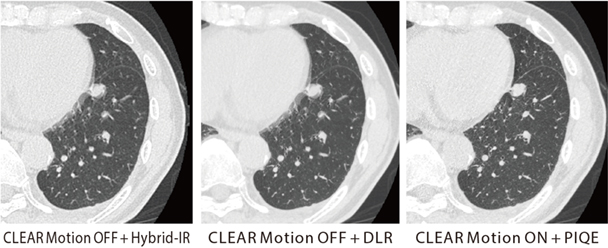

CLEAR Motion(図2)などで質の高い検査を迅速に提供

CLEAR Motionについては、CardiacとBodyの両方で使用している。稲垣係長は、「大動脈解離を疑い、従来であれば心電図同期が必要な症例でも、Aquilion ONE / INSIGHT Editionではガントリの回転速度やヘリカルスキャンも高速化していることに加えて、CLEAR Motionをかけることで心拍動によるアーチファクトを抑えて、ブレのない画像が得られます。スループットも向上しており、患者さんにとっても有用な検査が提供できます」と評価する。

図2 原発性肺がん、肺転移症例で経過観察中

PIQE+ CLEAR Motionの併用で、心拍動に伴うアーチファクトを低減し、高い時間分解能かつ高精細画像の両立が期待できる。